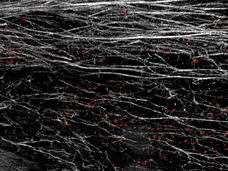

Tumors May Shed Protein to Create Barriers that Block Immune Cells

Cancer cells can shed a protein called DDR1 that helps collagen proteins create dense barriers around tumors. A study in mice showed these barriers can prevent immune cells from entering and killing tumors.